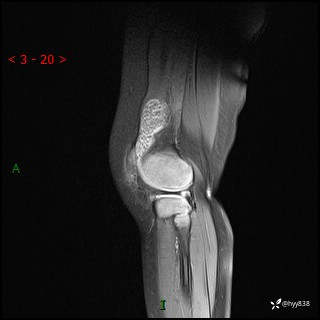

现病史:患儿1月前无明显诱因出现左下肢跛行,伴左膝关节红肿,无发热、咳嗽、恶心、呕吐等症,于当地医院就诊行X线片未提示异常,今至我院门诊就诊,门诊医师拟“跛行待查”收入院。 病后,患儿精神、食欲可,睡眠欠安,大小便通畅,体力体重无明显下降。

左膝MRI平扫